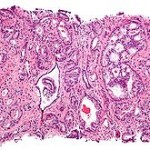

Gli scienziati hanno identificato una proteina che regola l’attivazione del grasso bruno sia nel cervello che nei tessuti del corpo. La ricerca è stata pubblicata sulla rivista Cell. A differenza del grasso bianco che funziona principalmente per immagazzinare il grasso, il grasso bruno (noto come tessuto adiposo bruno), brucia i grassi per produrre calore in un processo chiamato termogenesi. La ricerca, condotta dagli scienziati dell’Università di Cambridge, ha scoperto che la proteina BMP8B, agisce su un sistema metabolico specifico che opera nel cervello e nei tessuti del corpo, per regolare il grasso bruno e che per questo, potrebbe diventare un bersaglio terapeutico importane nel trattamento della perdita di peso. Secondo i ricercatori, l’attivazione del grasso bruno potrebbe contribuire a sostenere i programmi di perdita di peso. Una caratteristica importante delle attuali strategie per la perdita di peso è che i pazienti perdono molto peso nella fase iniziale, ma non riescono in seguito a mantenere il peso raggiunto pur continuando la stessa dieta. Questo accade perchè il corpo umano è molto bravo a rilevare la riduzione del consumo di cibo che compensa rallentando il tasso metabolico.Una strategia per aumentare l’attività del grasso bruno potrebbe potenzialmente essere utilizzata in combinazione con gli attuali programmi di perdita di peso, per prevenire la riduzione del tasso metabolico. la ricerca ha dimostrato che il trattamento con la proteina BMP8B porta alla perdita di peso : favorisce il grasso bruno che brucia più calorie.